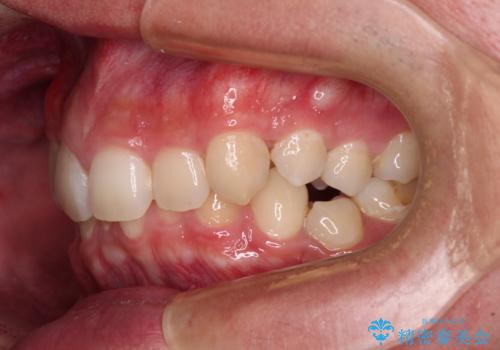

- 「前歯のデコボコが気になる」「前歯の中心がずれていて気になる」とご相談に来られた患者様の症例です。

診察の結果、上下の歯が並ぶためのスペースが不足しており、特に上顎右側の側切歯が内側(口蓋側)に転移していたため、正中が大きく右にずれている状態でした。

上下左右の第一小臼歯を抜歯してスペースを確保する計画を立てました。